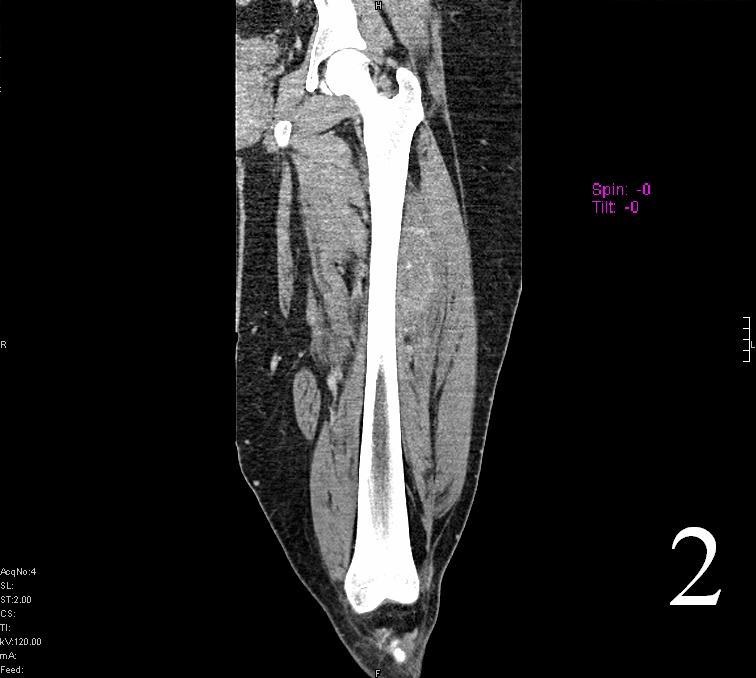

CT

• Shows attenuation similar to the muscle

• May be heterogenous with areas of necrosis and hemorrhage

Fig. 1

Fig. 2

Fig. 1-2 Axial (Fig. 1) and coronal CT (Fig. 2) reconstruction of the femur and thigh shows an Extraskeletal Ewing Sarcoma arising in the soft tissues adjacent to the femur